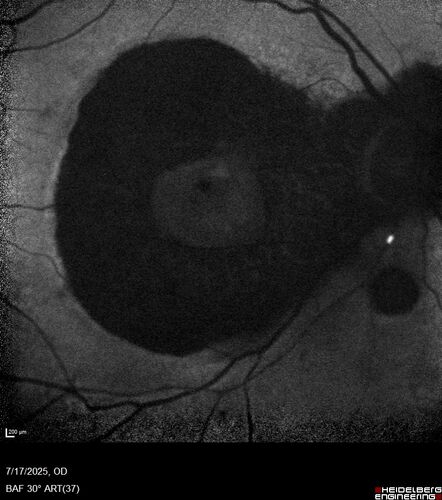

BRAO - plaques in vessels - GIF video of FA

78 year old female with vision loss for 1 week and old macular scar. Images show BRAO with plaques and FA shows occlusion.

BRAO_126199_071725_11.jpg

BRAO and macular scar - plaques in vessel and video